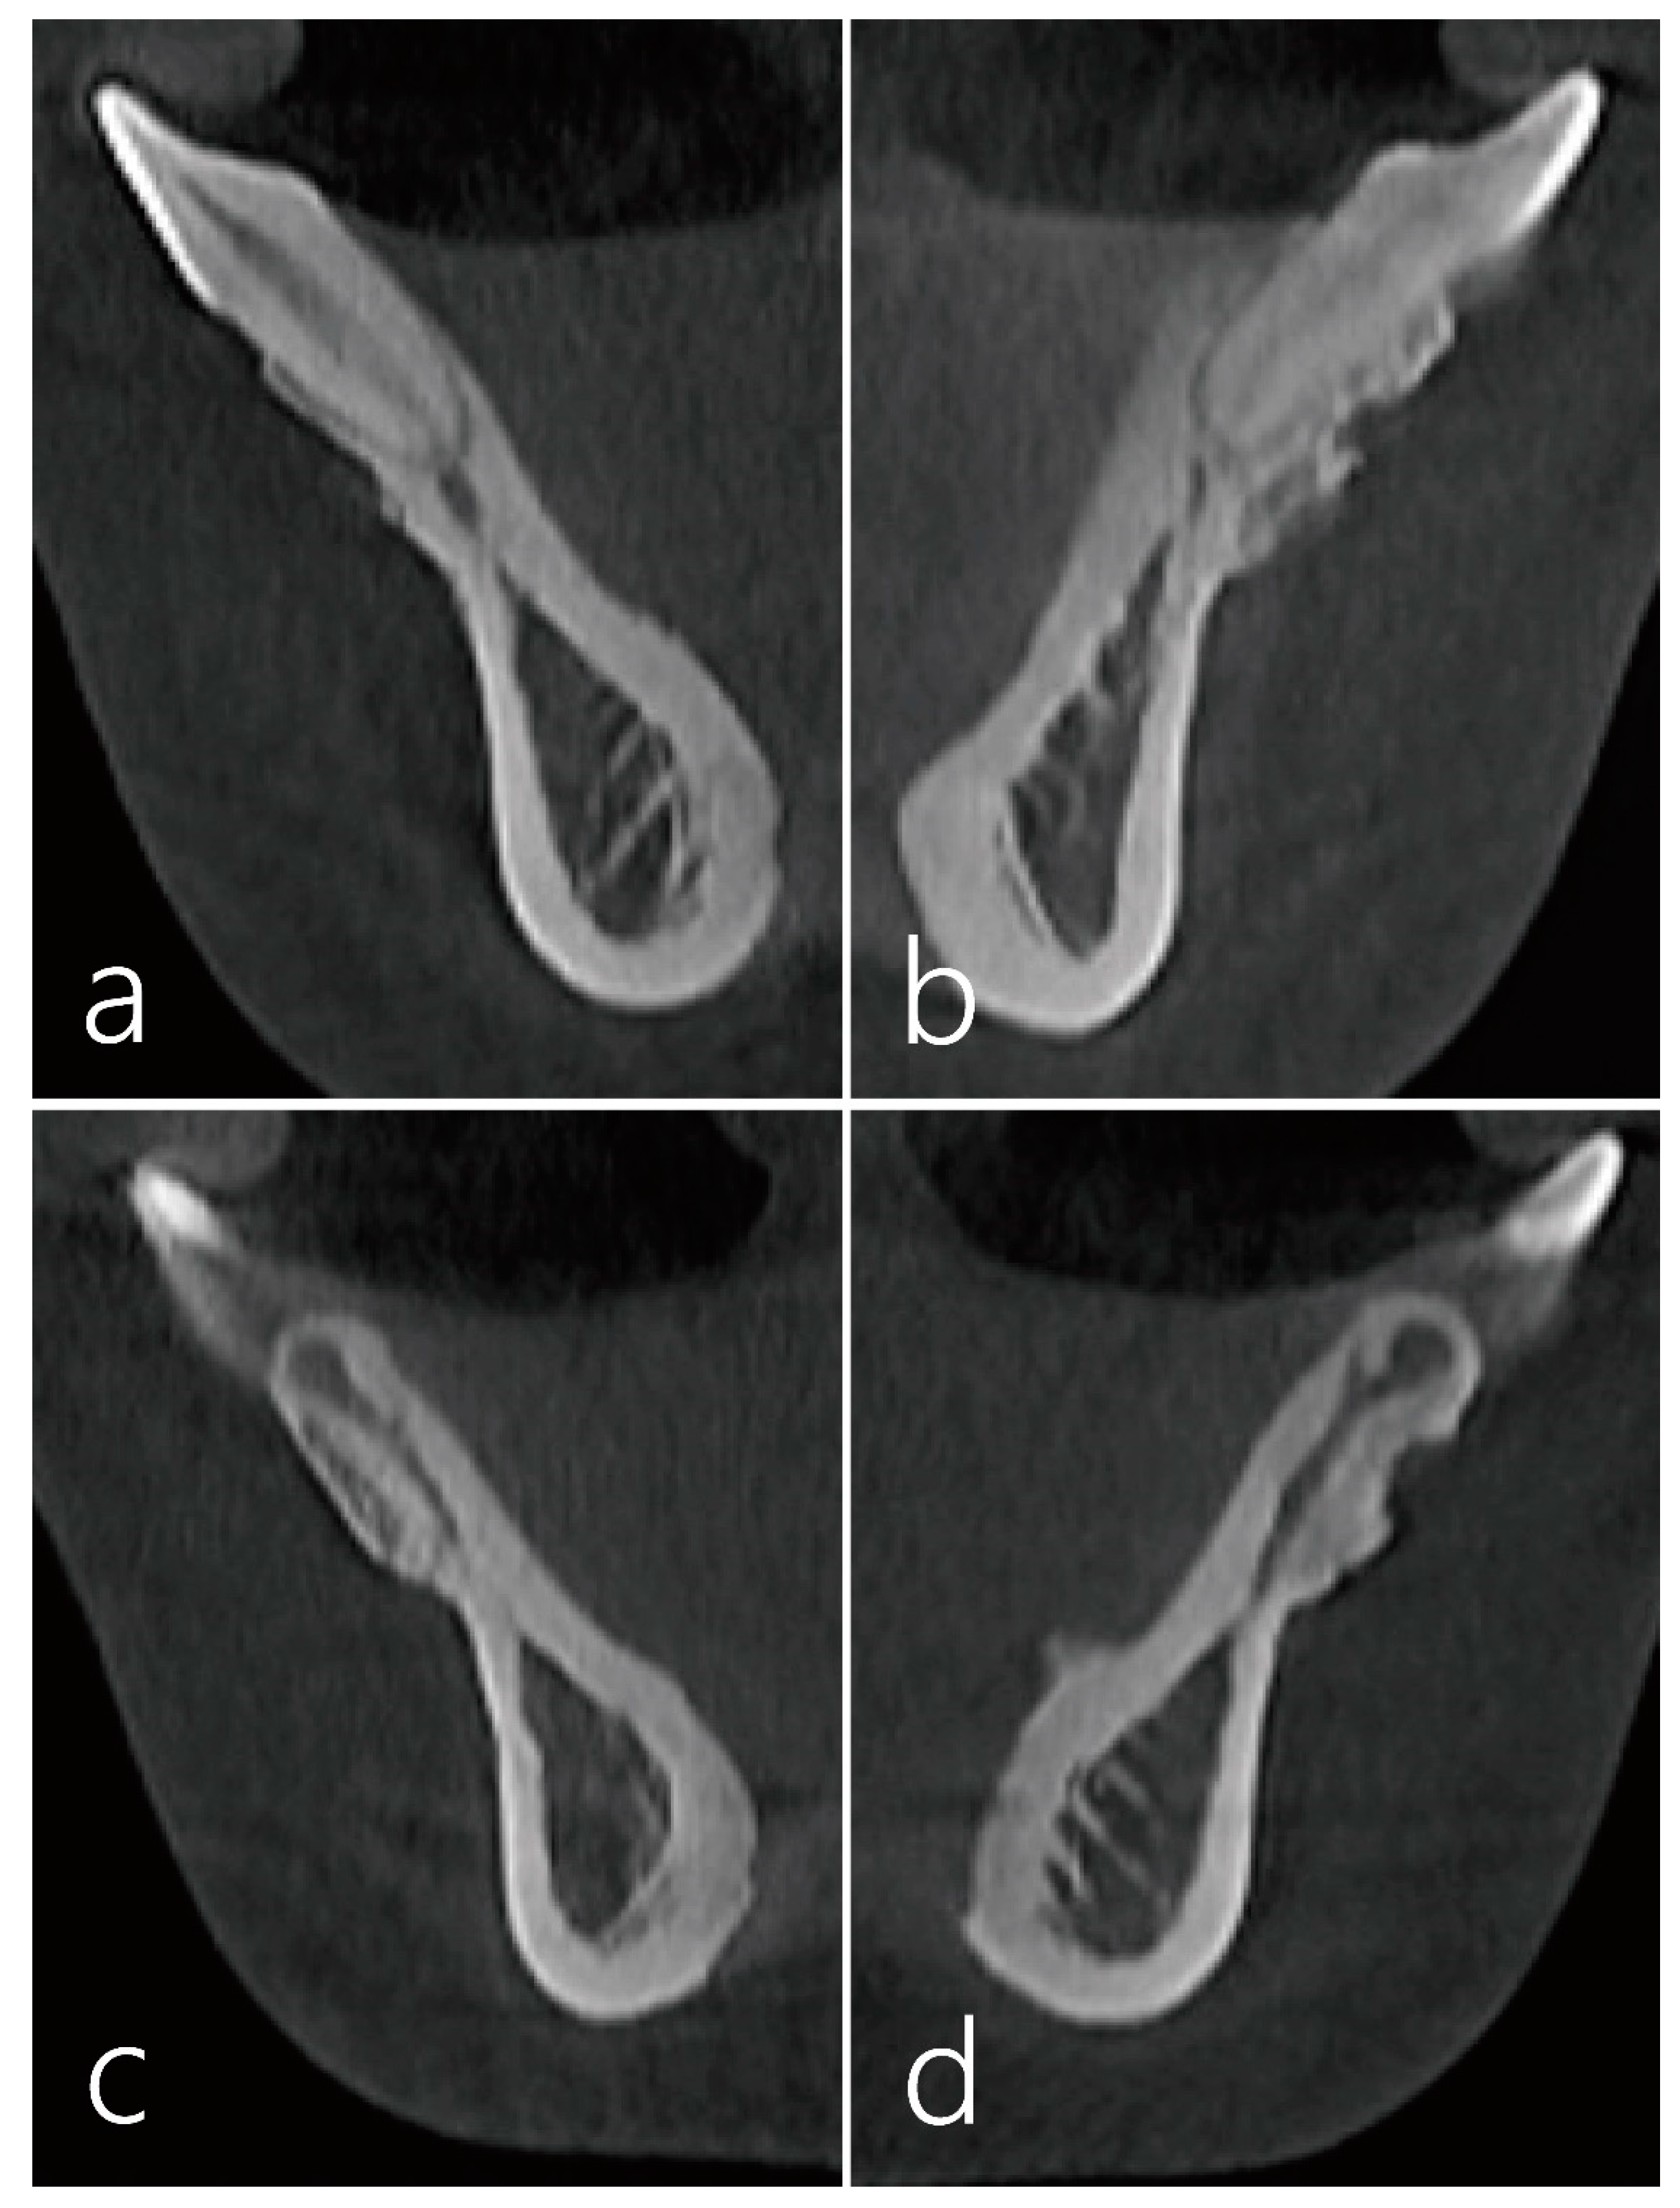

2. Case Report